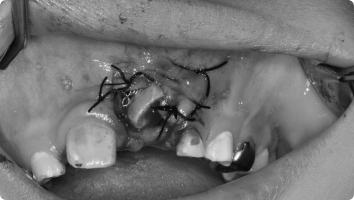

- 국소마취 후, 치아가 묻혀 있는 잇몸을 작게 열어 치아 머리(치관)를 노출시킵니다.

- 치아 표면에 교정용 버튼(장치)을 부착하고, 교정력(작은 고무줄·와이어)을 이용해 치아를 이동시킵니다.

- 수술 자체는 짧고 안전하게 진행되며, 이후에는 교정치료와 병행하여 서서히 치아가 배열됩니다.